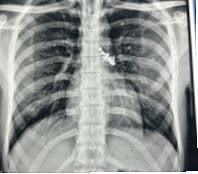

शुद्धीवर आल्यानंतर, त्याला 2 ते 3 मिनिटे तीव— खोकला, छातीत वेदना आणि श्वास घेण्यास अडथळा जाणवू लागला. डॉक्टरांनी तातडीने एक्स-रे काढल्यावर फुफ्फुसात पाच आणि पोटात दोन स्क्रू असल्याचे स्पष्ट झाले. सुदैवाने, स्क्रू मुळे श्वसननलिकेला गंभीर दुखापत झाली नव्हती.

त्याला डीपीयू सुपरस्पेशालिटी हॉस्पिटलच्या आपत्कालीन विभागात दाखल केले होते. येथील प्राध्यापक व श्वसनरोग विभागाचे प्रमुख डॉ. एम. एस. बर्थवाल आणि त्यांच्या पथकाच्या नेतृत्वाखाली हे स्क्रू काढण्यासाठी सखोल नियोजन केले. कमी खर्चिक आणि कमी त्रासदायक असलेल्या फ्लेक्सिबल एअर-वे तंत्राचा त्यासाठी वापर केला. तसेच, ही शस्त्रक्रिया यशस्वीपणे पार पाडली. तीन तास चाललेली प्रक्रिया अत्यंत आव्हानात्मक ठरली. सर्व पाच स्क्रू डाव्या फुफ्फुसाच्या वरच्या भागातील श्वसनलिकेत अडकले होते. रुग्णाला भूल देऊनही त्याला होणार्‍या सततच्या खोकल्यामुळे त्याच्या स्थितीत बदल होत होता. विशेष रॅट-टूथ आणि डॉर्मिया बास्केट फोर्सेप्ससारख्या प्रगत उपकरणांच्या मदतीने सर्व पाच स्क्रू यशस्वीपणे काढण्यात आले. प्रक्रियेदरम्यान, एक स्क्रू ओरोफॅरिंक्समध्ये सरकून रुग्णाने गिळला. मात्र, पुढील 48 तासांत पोटातील दोन स्क्रू नैसर्गिकरित्या बाहेर पडले.